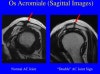

견봉골(Os Acromiale)

Failure of one of the acromial ossification centers to fuse.

It is present in 5% of the population. Usually it is regarded as a normal variant.

It may cause impingement because if it is unstable, it may be pulled inferiorly during abduction by the deltoid, which attaches here.